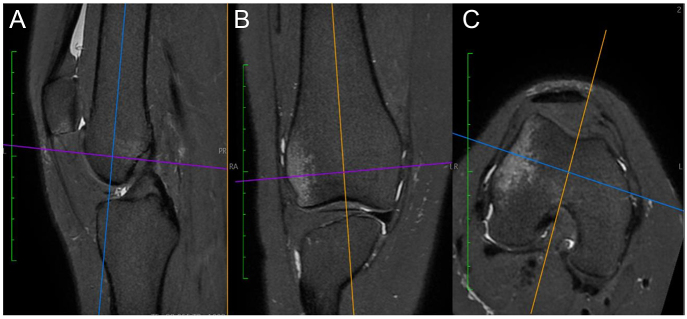

Patellar dislocations present predominantly during adolescence, with a higher incidence observed among female patients. Patellofemoral joint stability depends critically on both osseous anatomy and soft tissue structures. Patellofemoral pathology can be classified into three major groups: objective patellar instability OPI, potential patellar instability and painful patellar syndrome. Three primary risk factors predispose individuals to patellar dislocation: trochlear dysplasia, patella alta and increased tibial tuberosity-trochlear groove (TT-TG) distance. Three secondary risk factors should be considered: femoral and tibial rotational abnormalities and valgus deformity. MRI has become the imaging modality of choice, enabling precise quantification of OPI risk factors in a single imaging examination. The 'menu à la carte' approach guides the treatment of OPI by addressing the most relevant anatomical risk factors for each patient using statistical thresholds.